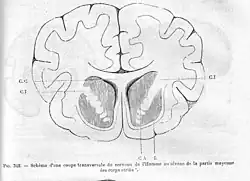

La capsule interne est une épaisse lame de matière blanche du cerveau située entre le thalamus et le noyau caudé d'une part, et le noyau lenticulaire d'autre part. Les axones du faisceau pyramidal passent dans la partie postérieure de la capsule interne.